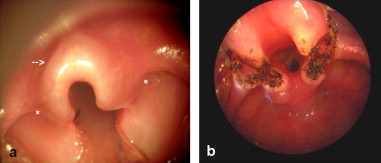

Diagnostic Flexible Nasopharyngolaryngoscopy (FNPLS) is a procedure used to visualize the larynx and assess the structural integrity of the tissues. During the procedure, a flexible scope is inserted through the nose or mouth and passed down into the throat to reach the larynx. This allows the healthcare provider to directly observe the larynx and identify any abnormalities.

In the case of laryngomalacia, laryngoscopy often reveals specific findings that confirm the diagnosis. The most common finding is the collapse of the supraglottic structures, which include the epiglottis, aryepiglottic folds, and false vocal cords. These structures may appear floppy, redundant, and prolapsed, leading to partial obstruction during breathing. The degree of collapse can vary, ranging from mild to severe.

In addition to assessing the structural aspects, laryngoscopy may also help identify any other associated conditions or anatomical abnormalities (secondary airway lesion/SAL) that could contribute to the symptoms. It allows the healthcare provider to evaluate the movement of the vocal cords, assess the presence of any anatomical obstructions, and determine the overall impact on breathing.